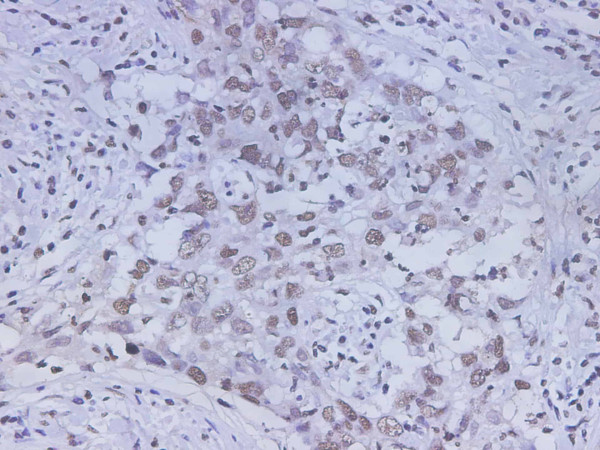

Product information "Anti-HMGB-1"

Human High-mobility group box 1 protein (HMGB1), previously known as HMG-1 or amphoterin, is a member of the high mobility group box family of non-histone chromosomal proteins. Human HMGB1 is expressed as a 30 kDa, 215 amino acid (aa) single chain polypeptide containing three domains: two N-terminal globular, 70 aa positively charged DNA-binding domains (HMG boxes A and B), and a negatively charged 30 aa C-terminal region that contains only Asp and Glu. Residues 27?43 and 178?184 contain a NLS. Posttranslational modifications of the molecule have been reported, with acetylation occurring on as many as 17 lysine residues. HMGB1 is expressed at high levels in almost all cells. It was originally discovered as a nuclear protein that could bend DNA. Such bending stabilizes nucleosome formation and regulates the expression of select genes upon recruitment by DNA binding proteins. It is now known that HMGB1 can also act extracellularly, both as an inflammatory mediator that promotes monocyte migration and cytokine secretion, and as a mediator of T cell-dendritic cell interaction. The cytokine activity of HBMG1 is restricted to the HMG B box, while the A box is associated with the helix-loop-helix domain of transcription factors. HMBG1 is released in response to cell death and as a secretion product. Although HMBG-1 does not possess a classic signal sequence, it appears to be secreted as an acetylated form via secretory endolysosome exocytosis. Once secreted, HMGB1 transduces cellular signals through its high affinity receptor, RAGE and, possibly, TLR2 and TLR4. Human HMGB1 is 100% aa identical to canine HMGB1 and 99% aa identical to mouse, rat, bovine and porcine HMGB1, respectively. Protein function: Multifunctional redox sensitive protein with various roles in different cellular compartments. In the nucleus is one of the major chromatin-associated non-histone proteins and acts as a DNA chaperone involved in replication, transcription, chromatin remodeling, V(D)J recombination, DNA repair and genome stability (PubMed:33147444). Proposed to be an universal biosensor for nucleic acids. Promotes host inflammatory response to sterile and infectious signals and is involved in the coordination and integration of innate and adaptive immune responses. In the cytoplasm functions as a sensor and/or chaperone for immunogenic nucleic acids implicating the activation of TLR9-mediated immune responses, and mediates autophagy. Acts as a danger-associated molecular pattern (DAMP) molecule that amplifies immune responses during tissue injury (PubMed:27362237). Released to the extracellular environment can bind DNA, nucleosomes, IL-1 beta, CXCL12, AGER isoform 2/sRAGE, lipopolysaccharide (LPS) and lipoteichoic acid (LTA), and activates cells through engagement of multiple surface receptors (PubMed:34743181). In the extracellular compartment fully reduced HMGB1 (released by necrosis) acts as a chemokine, disulfide HMGB1 (actively secreted) as a cytokine, and sulfonyl HMGB1 (released from apoptotic cells) promotes immunological tolerance (PubMed:23446148, PubMed:23519706, PubMed:23994764, PubMed:25048472). Has proangiogdenic activity. May be involved in platelet activation. Binds to phosphatidylserine and phosphatidylethanolamide. Bound to RAGE mediates signaling for neuronal outgrowth. May play a role in accumulation of expanded polyglutamine (polyQ) proteins such as huntingtin (HTT) or TBP (PubMed:23303669, PubMed:25549101). [The UniProt Consortium]

| Application: | IHC |